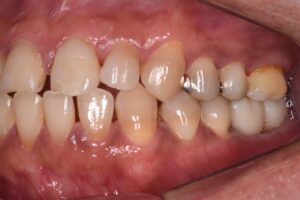

こんにちは!中津まさデンタルクリニックです。 こちらの患者様は、奥歯がなく噛みにくいとの主訴でした。 そのため、周りの歯を治療したあとにインプラントを埋入し奥歯で噛みやすい環境をつくりました。 症例によっては長期の治療に […]